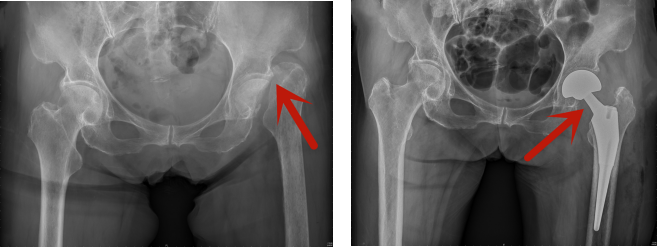

术前、术后对比:股骨颈骨折术前影像;半髋关节置换术后影像

患者今年83岁,因不慎摔伤导致左侧股骨颈骨折,付立功主治医师在接诊后,考虑患者高龄,且股骨颈骨折移位明显,以后一定会发生骨股头缺血性坏死,影响患者行走及日常生活。结合老人的身体状况及骨折类型,付立功医师立即决定为患者行直接前方入路半髋关节置换术。

传统的后外侧入路髋关节置换术,切口长,手术中需离断后方的外旋肌群,包括梨状肌、闭孔内肌、上下孖肌、闭孔外肌、股方肌等,创伤较大,且术后在上述结构未愈合前,髋关节向后脱位的风险明显增加,特别是髋关节屈曲超过90°时。因此患者在接受传统后外侧入路手术后,需要长期保持半卧位,不能坐直,非常影响患者的日常生活,如无法坐着吃饭、坐座便器、穿鞋袜、坐一些比较矮的凳子等,术后很长时间内无法生活自理。而直接前方入路的手术,切口小,且经肌肉间隙完成手术,不损伤任何肌肉组织,对患者创伤小,术后恢复快。由于该入路不损伤后方的关节囊和肌肉组织,髋关节向后脱位的风险大大降低,因此术后早期就允许患者坐直,甚至超过90°。患者第二天就可以下地行走,并且可以自由活动,不受任何活动限制,日常生活基本不受影响,极大地提高了术后早期生活自理能力。